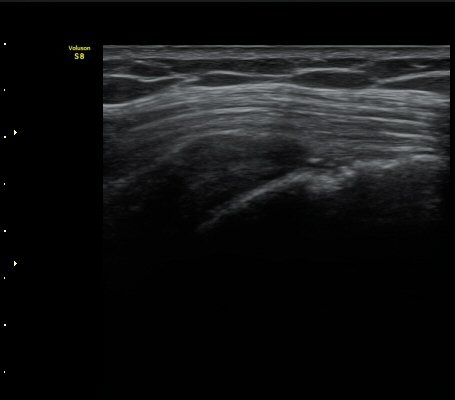

¾î±ú ±Ø»ó°Ç ÃÊÀ½ÆÄ°Ë»ó ±Ø»ó°Ç ºÎÂøºÎ°¡ °üÂûµÇÁö ¾Ê°í ±ÙÀ§ºÎ·Î ´ç°ÜÁ® ÀÖ´Ù(±×¸² 1, 2).

±Ø»ó°Ç Ⱦ´Ü¸é°Ë»ç»ó »ó¿Ï°ñµÎ¸¦ µ¤°í ÀÖ¾î¾ßÇÒ ±Ø»ó°ÇÀÌ º¸ÀÌÁö ¾Ê°í Á¡¾×³¶ÀÌ ÆíÆòÇϰÔ

³»·Á ¾É¾Æ º¸ÀδÙ(±×¸² 3).